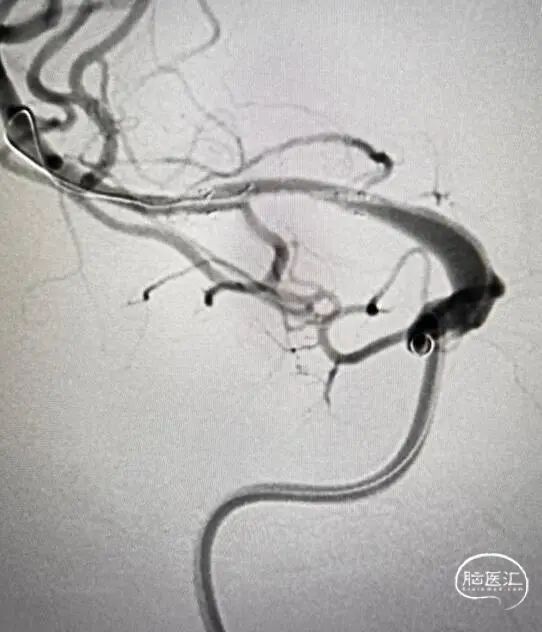

R-ICA造影示RM1闭塞,残端呈笔尖样(tapered sign),提示ICAD性质。

Syphonet® 4.0×30mm取栓支架释放,造影可见M1原位重度狭窄及远端血栓影。

扩张后造影可见狭窄较前明显改善,远端血栓影仍清晰可见。

留置支架微导管,经中间导管造影见残余狭窄较前加重。

支架释放后可见原位血栓,动脉推注替罗非班后稍好转。

微导丝携球囊通过支架,拟后扩张,再次造影示原位血栓消失。

残余狭窄明显改善,经观察血流稳定。